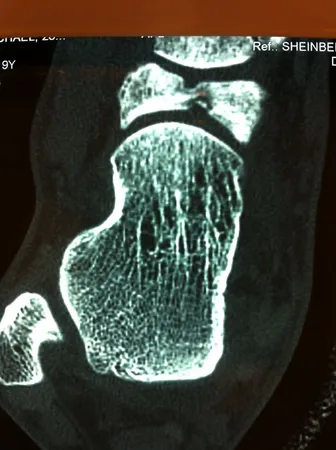

Stress fractures of the navicular are relatively common injuries that occur in athletes. They are more common in sports that require a lot of sprinting or running on the ball of the foot. They are very subtle injuries that are often misdiagnosed as an ankle sprain. Patients usually present with pain across the top part of the foot just in front of the ankle. It is often vague in nature and pain is present more commonly in the mid or later part of an activity. Over time an athlete would have a difficult time running on the foot. These fractures need to be identified and treated as early as possible. X-rays may be negative in the initial presentation. It may require an MRI to evaluate the navicular. If there is bone marrow edema of the bone without any fracture line, then this can be treated conservatively with a short course of nonweightbearing in a boot or cast. If there is a suggestion that there is a fracture of the navicular, CT scans are important to get the full extent of the injury. If evaluated and treated early, stress fractures can heal with a conservative approach. A minimum of eight weeks nonweightbearing in a cast is important. These fractures may take 3-4 months before they heal. In some cases, the fracture does not heal and the problem becomes more chronic. Patients are then given the choice of doing a surgical procedure to correct the problem. If the margins of the bone are hard and sclerotic limiting the blood supply to the area then these margins need to be removed and bone grafted. A small plate or screws are then applied to the area to allow the area to heal primarily. This would require the athlete to be off from running sports for 4-12 months. Follow up examinations with a CT scan may be necessary to fully evaluate the healing process.